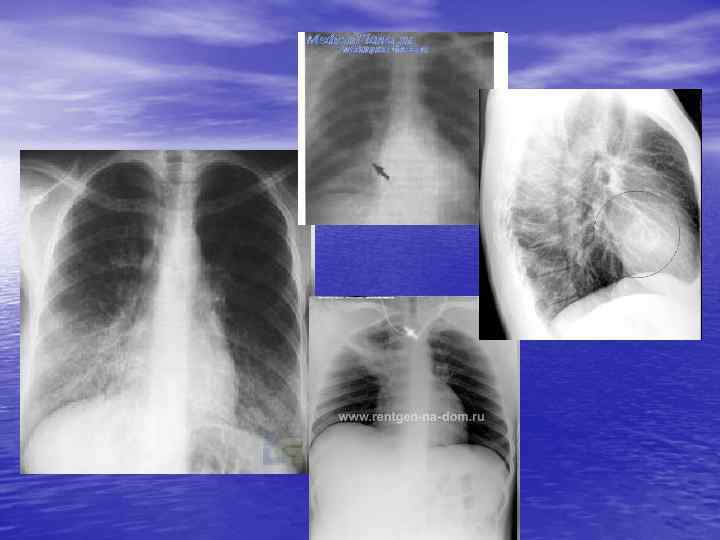

Ексудативний плеврит Міждолевий плеврит

Синдром утворення порожнини в легені киста легені абсцес легені після прориву в бронх

Вроджена киста правої легені

Пневмоторакс